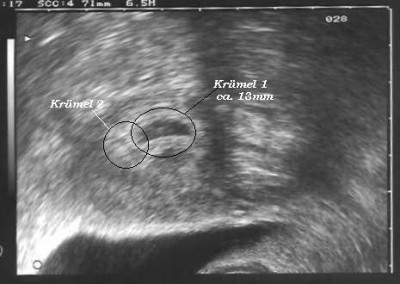

ich bin ganz aufgeregt, wir kommen gerade vom US beim Prof. er hat eine Fruchthöle gesehen mit Inhalt, er meinte er sieht den Dottersack und die entwicklung wäre gut (Zeitgemäß). Stellt Euch vor er hat noch eine 2. Fruchthöhle gesehen, die ist etwas kleiner konnte aber nicht sagen ob da auch was drin ist. Vieleicht bekommen wir ja doch 2 :baby: :baby: :juhu: :juhu: :juhu: Ich kann es garnicht glauben, es wäre so schön. Wobei ich schon Angst vor einer Zwillingsschwangerschaft habe, weil da doch mehr pasieren kann, bzw. die Babys meisten früher kommen.

2ab.JPG

US 16.07.07 2 Herzlein schlagen Zwillinge